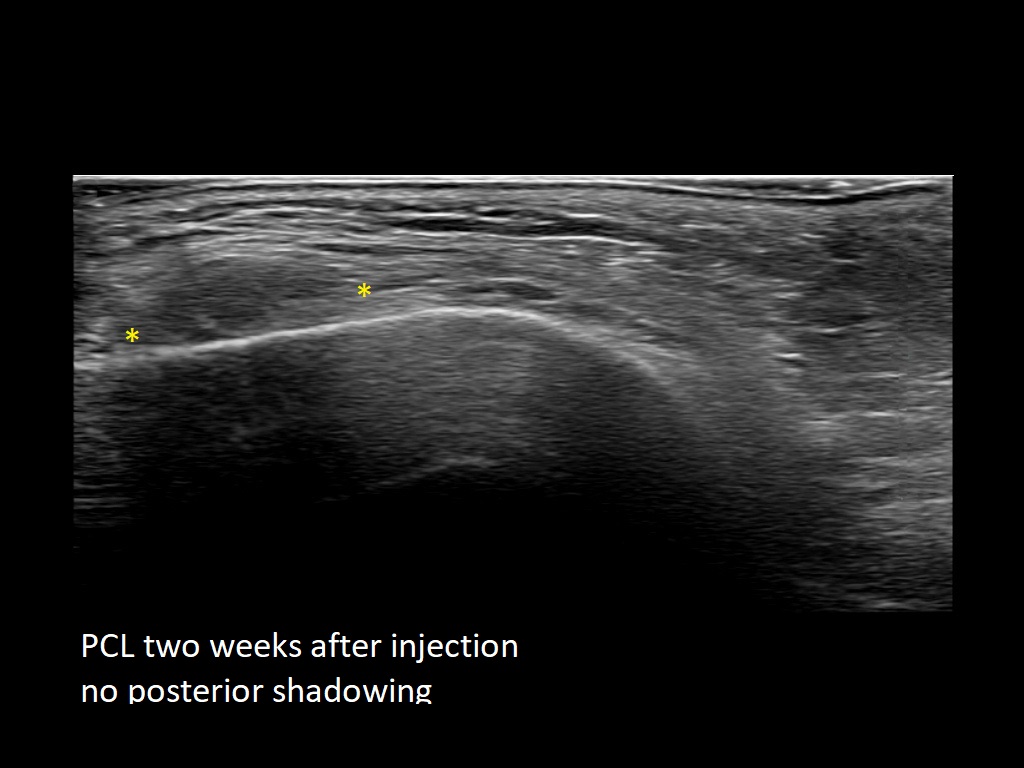

PCL 0

PCL 10a

PCL 11a

PCL 12a

PCL 13a

PCL 14a

PCL 15a

PCL 16a

PCL 1a

PCL 2a

PCL 3a

PCL 3b e

PCL 4a

PCL 4b e

PCL 5a

PCL 5b e